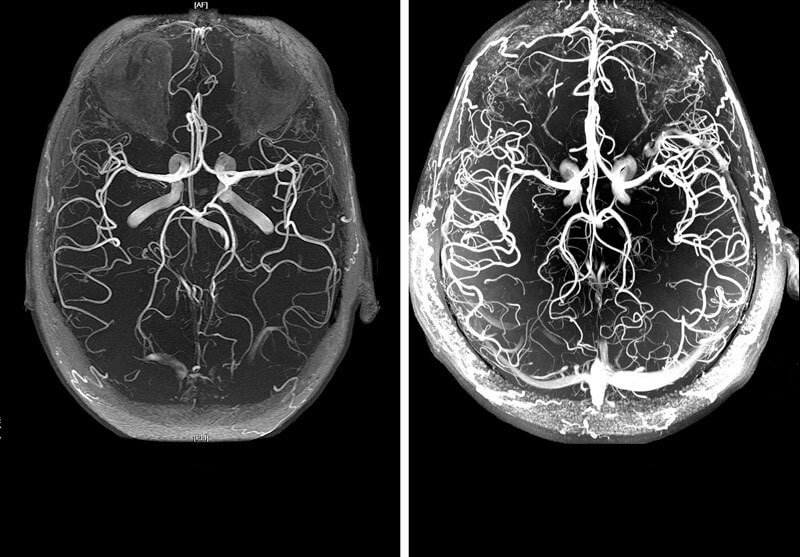

• Vasos sanguíneos del cerebro

El colesterol, que provoca la aterosclerosis de los vasos cerebrales, modifica tanto los vasos intracraneales como los extracraneales. La intensidad de los síntomas patológicos está directamente relacionada con el grado y la localización de las lesiones.

Además de la complicación más peligrosa, el ictus, puede haber depresión del SNC, desarrollo de trastornos mentales, pérdida de visión y deterioro de la memoria.

Brain stroke

Los síntomas iniciales de la lesión aparecen a partir de los 40-45 años.

En esta fase, pueden producirse "ataques isquémicos", acompañados de alteraciones sensoriales, trastornos del movimiento, anomalías de la visión, la audición y el habla. A pesar de la gravedad de los síntomas, son transitorios, reversibles y desaparecen por sí solos tras una única limpieza de los vasos sanguíneos con nutracéuticos.

El daño aterosclerótico grave puede provocar un accidente cerebrovascular, es decir, la necrosis del tejido cerebral. La sintomatología es la misma que en el caso anterior, pero no hay una mejora significativa después de la necrosis.

El cerebro también es responsable de la realización de las funciones mentales superiores. Por lo tanto, la formación de placas también conduce a una disminución de la inteligencia y la memoria y a cambios en el carácter (labilidad emocional, capricho, pereza). En ausencia de para limpiar los vasos sanguíneos de placas, esta lesión conduce al desarrollo de la demencia: la enfermedad de Alzheimer. Estas lesiones pueden provocar discapacidades o ser mortales.

El ictus se presenta en 2 formas:

• isquémico;

• hemorrágico.

El isquémico está causado por la oclusión del lecho vascular por un trombo; la causa del hemorrágico es la rotura de un vaso cerebral.